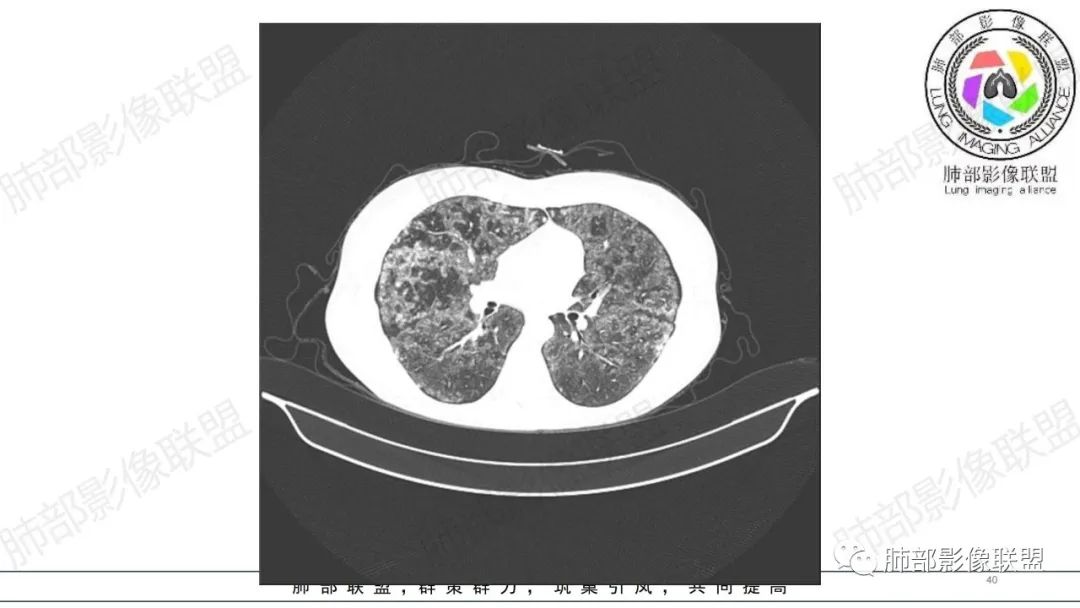

34岁女性患者,“哮喘”病史30年,近期有可疑刺激性气体吸入史;因乏力半年,咳嗽、憋气、发热4天就诊;6.1CT提示双肺广泛毛玻璃影及粟粒样结节,胸膜下闲置及血管周闲置,可见树丫征,部分小叶间隔增厚。考虑:1.过敏性肺泡炎,有可疑刺激气体接触史,胸膜下闲置,广泛毛玻璃影,地图样分布,粟粒结节边界模糊,支持过敏性肺泡炎,但糖皮激素治疗效果不佳,且动态复查血常规血红蛋白进行性降低,过敏性肺泡炎 不符合;2.肺含铁血黄素沉积症:患者30“哮喘”病史,可能为肺含铁症状,肺部CT提示双肺弥漫毛玻璃影及粟粒结节影,中下肺明显,肺底部分小叶间隔增厚,近期咳嗽、憋气、发热,血常规血红蛋白进行性下降,考虑肺含铁急性期症状,但临床无咯血症状,肺含铁不典型。综合考虑:肺含铁血黄素沉积症>过敏性肺泡炎。

年轻女性 ,急性喘息发热,肺部影像弥漫磨玻璃密度,部分细小腺泡结节,胸膜下黑线显示,短期复查,病变密度增高,下肺明显,血管周围肺组织累及较少、且逐渐成小叶间隔分布。考虑弥漫肺泡内病变,并经淋巴道转移,下肺比上肺明显,多为免疫细胞功能下肺较强。1.过敏性肺泡炎,有相关病史,三层密度特点、头尾测分布,符合。2 肺泡微石症,多有钙化,且缓慢起病,病程不太符合,放待排。3 吸入相关肺损伤,有病史,疾病演变过程也符合渗出-肉芽肿改变,建议详细询问病史。4 感染性病变,结核?病变气道分布为主,如此弥漫且没有树丫不符合。5.巨细胞病毒,可以磨玻璃 结节 改变,没有免疫缺陷病史。最后考虑吸入所致 1过敏性肺泡炎、吸入性肺损伤 鉴别肺泡微石症。